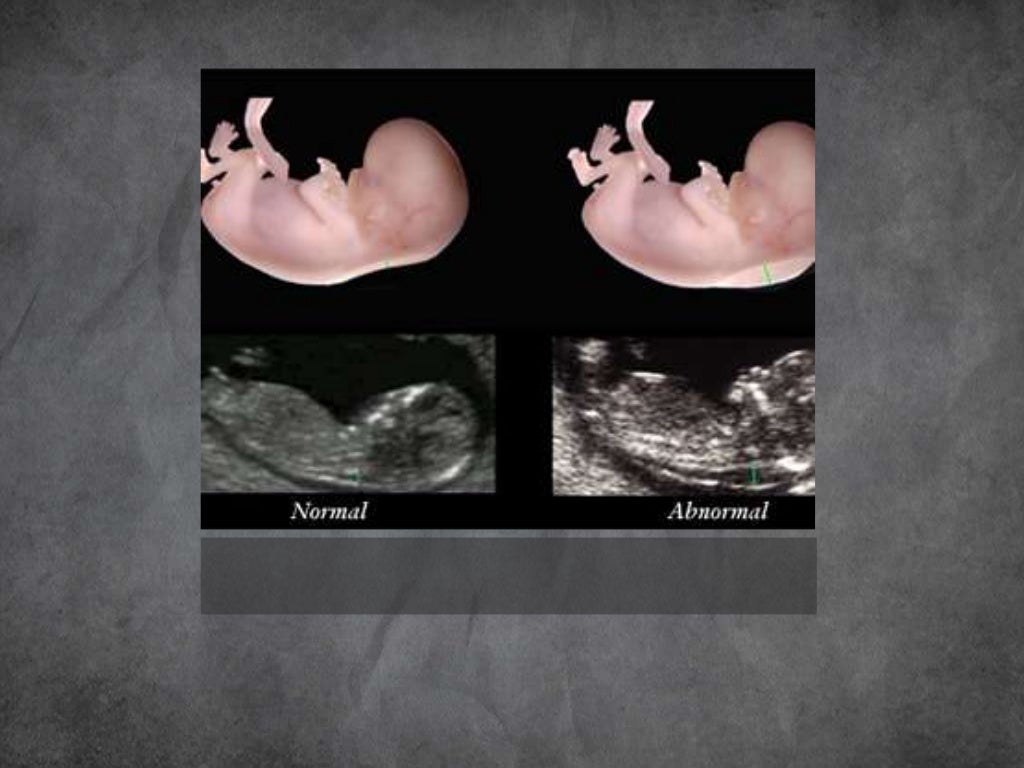

Imaging In Obstetrics First, Mid And Third trimester Ultrasound

Imaging In Obstetrics First, Mid And Third trimester Ultrasound Diagnostic Imaging Obstetrics Woodward Obstetrics, fourth edition, is an invaluable. Featuring approximately 260 diagnoses highlighting the most recent information, references, and images, this title serves as a. The newest edition of diagnostic imaging: The newest edition of diagnostic imaging: The newest edition of diagnostic imaging: Diagnostic Imaging Obstetrics Woodward.